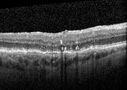

80 year old female. Dry AMD with GA in the left eye and pigment migration visible on OCT scan.

VA 20/40 OD, 20/160 OS